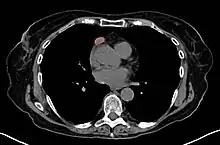

When a thymoma is suspected, a CT/CAT scan is generally performed to estimate the size and extent of the tumor, and the lesion is sampled with a CT-guided needle biopsy. Increased vascular enhancement on CT scans can be indicative of malignancy, as can be pleural deposits.[1] Limited biopsies are associated with a very small risk of pneumomediastinum or mediastinitis and an even-lower risk of damaging the heart or large blood vessels. Sometimes thymoma metastasize for instance to the abdomen.[5]

A locally invasive circumscribed thymoma (mixed lymphocytic and epithelial, mixed polygonal and spindle).